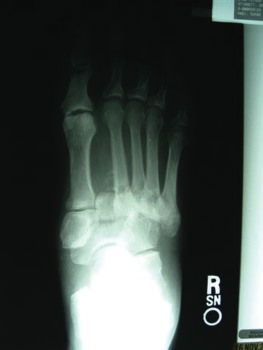

A 58-year-old patient with longstanding diabetes and a previous history of ulceration and neuropathy presented to the outpatient clinic with complaints of increasing redness and swelling to his right foot. He related that his primary care physician had seen him due to concern for a foot infection. However, the physician ordered X-rays and subsequently told the patient he had a fracture. The physician placed him on oral antibiotic therapy and sent him to the podiatry clinic for further workup. The patient denied any direct trauma to the foot or excessive changes in activity level. He complained of mild pain and admitted to fluctuating blood glucose levels. His past medical history was significant for diabetes, neuropathy and hypertension and no tobacco history. Physical examination revealed an obese male with palpable pedal pulses to the left foot and non-palpable dorsalis pedis on the right foot with a bounding posterior tibial pulse. He had absent protective and vibratory sensation bilaterally with increased skin temperatures to the right foot. The right foot was erythematous dorsal to the second through fifth metatarsals and edematous. We noted no ulcerations, macerations or fissures. Radiographs revealed dorsal dislocation at the tarsometatarsal joint, resulting in a divergence of the joint complex. We proceeded to emphasize cast immobilization until we achieved a reduction of edema and an equilibrium with the skin temperatures of the lower extremities. We continued the oral antibiotic therapy with Keflex in order to prevent infection due to deep bleeding from the fracturing or skin irritation from the edema. However, the tarsometatarsal was freely mobile and remained unstable during the four-week immobilization period. Due to the instability, we discussed surgical arthrodesis. We pursued this by using percutaneous Steinman pinning and a Synthes mini external fixator to add a structural framework around the fusion site. We added bone morphogenic protein at the arthrodesis sites to promote fusion. We subsequently emphasized non-weightbearing in a posterior splint and weekly clinic visits for pin care until the patient achieved radiographic union. At that time, we removed the fixation and initiated progressive weightbearing in a removable cast boot (i.e. CAM walker) for three to four weeks. We repeated radiographs and once we determined that the patient had maintained osseous integrity, we placed the patient in extra-depth shoes with custom-molded insoles for long-term maintenance. Dr. Hadi is an Associate with the Department of Podiatry of the MedClinic Medical Group in Sacramento, Calif. Dr. Steinberg (pictured) is an Assistant Professor in the Department of Surgery at the Georgetown University School of Medicine in Washington, D.C.